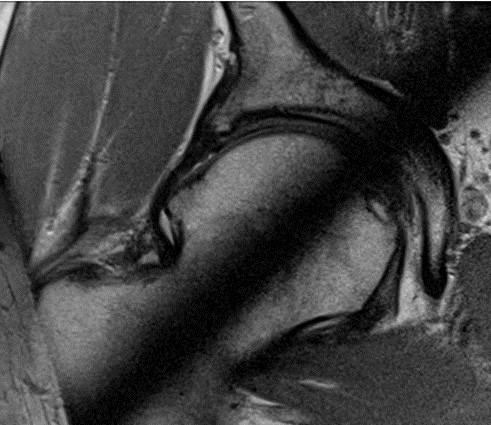

32-letni mężczyzna odczuwa ból biodra prawego, dotychczas dość intensywnie uprawiał sporty walki. Klinicznie: stwierdza się ograniczony bólem zakres ruchów z pomniejszeniem zgięcia, przywiedzenia i rotacji wewnętrznej. Obraz przekroju osiowego stawu biodrowego na przekroju zegarowym 12.00 - 18.00

Wskaż właściwe postępowanie lecznicze: